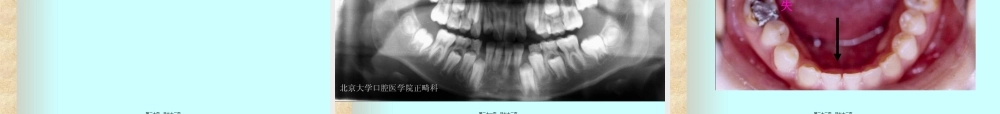

第一页,共七十二页。(zhǎngwò)第二页,共七十二页。(zhǒngzú)第三页,共七十二页。第四页,共七十二页。(二)后天(hòutiān)因素第五页,共七十二页。(三)功能因素第六页,共七十二页。(四)口腔不良习惯第七页,共七十二页。第八页,共七十二页。(yíchuán)第九页,共七十二页。遗传(yíchuán)因素:遗传(yíchuán)基因决定。第十页,共七十二页。错合畸形是随着人类(rénlèi)的种族演化(raceevolution)而发生和发展的80万~50万年前的古人头骨上未发现错合第十一页,共七十二页。1.原始人从爬行到直立第十二页,共七十二页。在单卵双生子,遗传特性几乎完全相同双卵双生子则与寻常弟兄一样,具表现的相同性状较少。第十三页,共七十二页。第十四页,共七十二页。第十五页,共七十二页。第十六页,共七十二页。第十七页,共七十二页。第十八页,共七十二页。(一)先天因素(congenitalcauses)第十九页,共七十二页。3.常见的发育障碍及缺陷ŻŻ第二十页,共七十二页。多生(duōshēnɡ)上颌侧切牙第二十一页,共七十二页。下切牙先天(xiāntiān)缺失第二十二页,共七十二页。3.常见的发育障碍(zhàngài)及缺陷第二十三页,共七十二页。唇系带附着(fùzhuó)异常第二十四页,共七十二页。中切牙间隙--唇系带附丽(fùlì)异常第二十五页,共七十二页。1.某些急性及慢性(mànxìng)疾病第二十六页,共七十二页。1.吮吸功能异常(yìcháng)第二十七页,共七十二页。1.吮指习惯ŻŻŻ第二十八页,共七十二页。所造成错合畸形(jīxíng)的类型与吮指部位、颊肌收缩的张力及吮吸时的姿势有关第二十九页,共七十二页。第三十页,共七十二页。第三十一页,共七十二页。继发舌习惯:吮指或口呼吸(hūxī)第三十二页,共七十二页。前牙开合(kāihé)第三十三页,共七十二页。舌刺矫治器第三十四页,共七十二页。舌刺矫治器第三十五页,共七十二页。阻生牙第三十六页,共七十二页。(xíguàn)第三十七页,共七十二页。使上前牙向唇侧倾斜移位出现牙间隙压下前牙向舌侧倾斜移位第三十八页,共七十二页。(xíngchéng)第三十九页,共七十二页。覆盖下唇继发性下唇卷缩第四十页,共七十二页。多发生在乳牙后期第四十一页,共七十二页。多见咬铅笔和啃指甲第四十二页,共七十二页。儿童睡眠时,经常用手、肘或拳头(quántóu)枕在一侧的脸下第四十三页,共七十二页。第四...